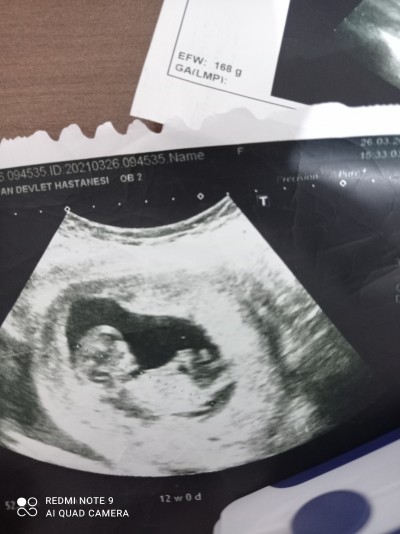

Kızlar ulstrasondan cinsiyet Tahmini yapabilir misiniz

image

Gebelik haftası 12+2